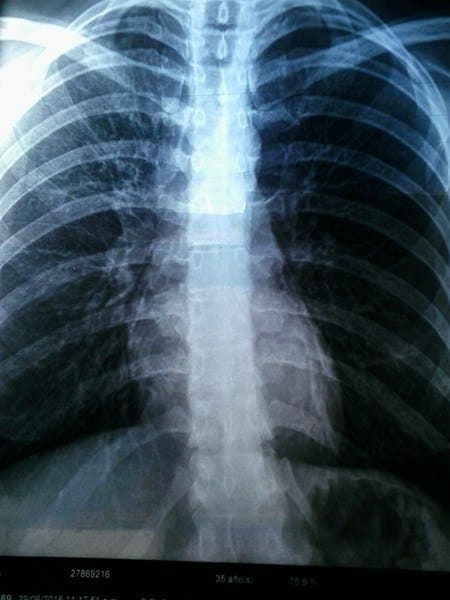

Hola, quisiera saber si algún doctor o estudiante de medicina puede observar esta radiografía de tórax y darme un diagnostico. Dos doctores la vieron y dieron dos diagnósticos diferentes, por eso me gustaría tener otra opinión. Esta placa fue sacada a raíz de una consulta a un neumonologo por mucha tos.

La información que das es escasa, por la radiografía parece de una persona que no es joven, fumador, asmático, bronquitico etc, entre las características radiológicas llama la atención que la trama pulmonar esta dibujada y las características radiológicas son de un enfisema pulmonar, El enfisema es una de las variantes del conocido EPOC (enfermedad pulmonar obstructiva crónica) la otra forma es la bronquitis crónica, en el primero los pacientes tienen falta de aire que se va incrementando con el tiempo y aparece cada vez más a esfuerzos habituales, el paciente en su fase avanzada, es delgado, con el tórax inflado de aire, respira con dificultad y adquiere un color rosado lo que se le llama en medicina el "soplador rosado", en el caso de la bronquitis crónica se considera cuando un paciente sufre episodios de tos y expectoración por más de tres meses en dos años consecutivos y adquiere características de hinchado, gordo, con cianosis, osea coloración azulosa (abotagado azul), en ambos casos la causa fundamenta es el tabaco, los irritantes respiratorios, también pueden ser una causa y se ha asociado al deficits congénito o familiar de alfa 1 antitripsina, pero la falta en tu relato de cosas importantes no me hace pensar, ni en asma, ni en problemas congénitos familiares, de cualquier forma en el EPOC, las pruebas funcionales respiratorias son muy importantes para clasificar su intensidad y poner tratamiento, esta enfermedad no se cura, pero el paciente mejora mucho, gana calidad de vida y evita las recaídas con el tratamiento, espero que te sirva lo explicado y te ayude, Jose Daniel

Muchas Gracias Jose por haberme contestado. Te comento que la radiografía es mía, y tengo 35 años. Soy fumadora, pero solamente 3 cigarrillos al día cuanto mucho, aunque es verdad que un solo cigarrillo hace mal. Uno de los doctores que vio la radiografía me dijo que había un poquito de mucosidad pero que era alergia de la época. Me dijo que me haga vapor y nada más. El otro doctor dijo que había indicios de un principio de asma, que por eso se debían mis ataques de tos, falta de aire, etc. me dio unos inhaladores para que use todos los días. Mi duda estaba en que estos diagnósticos fueron hechos hace 2 semanas casi y en estos días me situación no ha mejorado. Sigo con mucha tos, falta de aire, y cuando toso sale como mucosidad. Nuevamente muchas gracias por haberte tomado el trabajo de ver las fotos y comentar. Saludos

Ahora con los datos que me das, parece tratarse de un episodio de bronquitis, alérgica o estacional, muy frecuente en estos meses y que casi siempre tienen una base alérgica... la opción de asma bronquial es improbable, ahora las características del Rx, muestran cierto grado de enfisema, te repito que el diagnostico de enfisema, lleva otras pruebas, incuida una Tomografía de los pulmones... de entre los medicamentos que te están dando deben ser broncodilatadores y/o esteroides lo cual debería mejorar el cuadro y facilitar junto a abundante ingestión de líquidos la espectoracion, ahora si estas tomando algún antistaminico (antialérgicos), esos resecan las secreciones y no te ayudan mucho y solo deben usarse cuando la tos impide dormir o descansar por su intensidad, como ves sigo con dudas sobre lo que preguntas, pues nada sustituye una consulta frente a frente para esclarecer todas las dudas, espero que te sirva mi opinión y me mantengas informado.